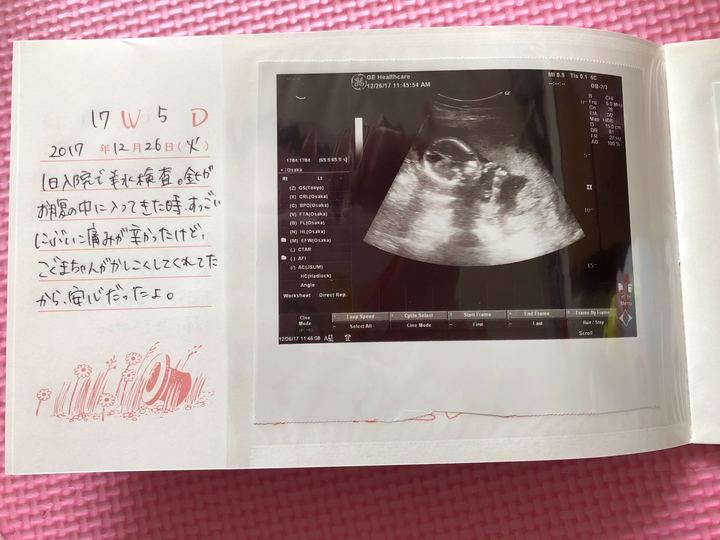

17週目に出生前診断(羊水検査)を受けました。

当時の心境を綴ったメモ

当時の心境を綴ったメモがありますので公開します。